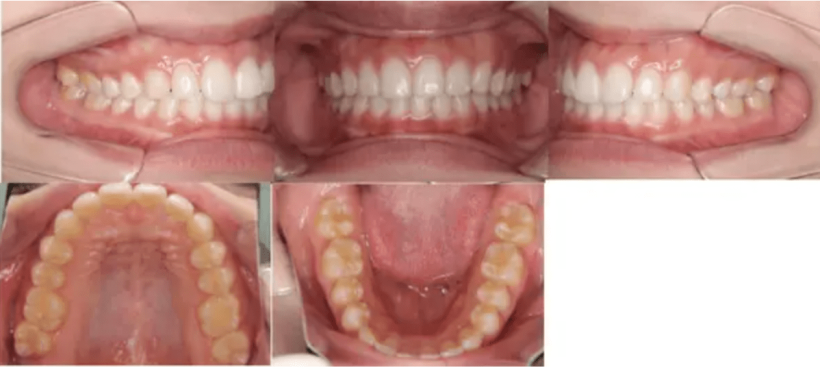

治療例①部分矯正: 28歳

主訴 前歯がガタガタである

治療内容 インビザライン・ライトを使用して主訴である前歯の交叉咬合を改善しつつ、下あご前歯のガタガタも改善した。

治療期間 10カ月

費用 40万円

【治療前】